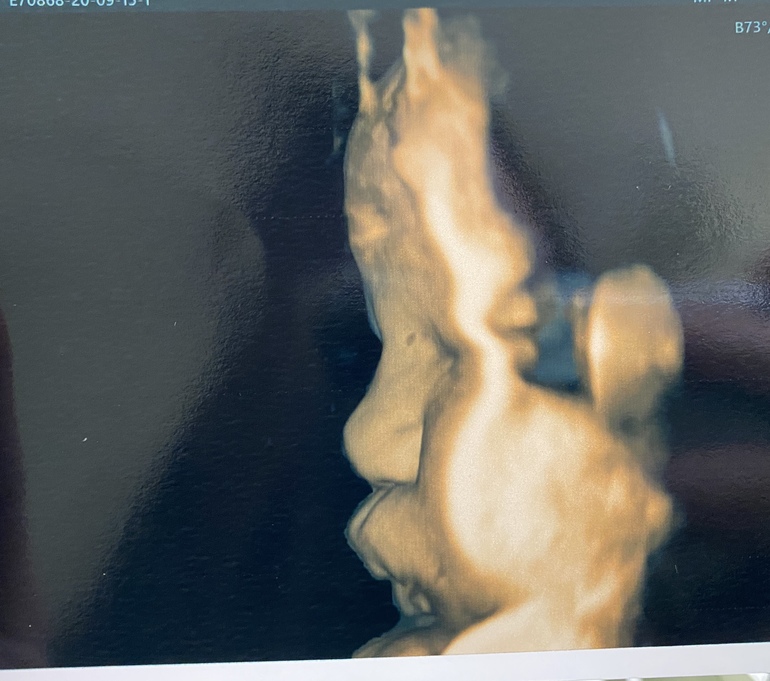

УЗИ, КТГ, доплерБыла сегодня на узи . Срок 38.3 и по месячным и по узи . Шейка 32 мм, зев сомкнут )степень зрелости Плаценты 2-3 ст . доча 3300 и 50 см . После узи пошла на осмотр к врачу . Шейка длинная , пропускает палец ) как долго я ещё буду хоть и есть ли шанс родить в пдр ?😄я уже отчаялась . Доче там видимо и так неплохо ) но ходить до 42 недель вообще нет никаких сил 😩